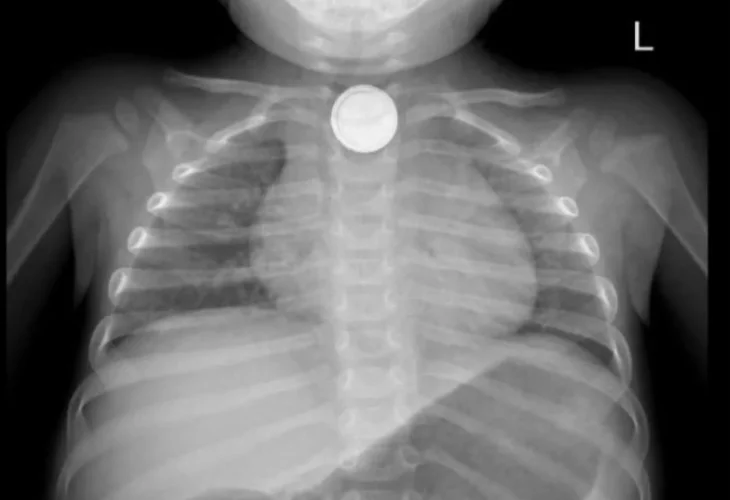

צילום הרנטגן שבו התגלתה הסוללה בוושט (צילום: אסותא אשדוד)המרכז הרפואי אסותא אשדוד דיווח היום (שני) כי ניצלו בשבוע האחרון חייו של פעוט, אשר בלע סוללת ליתיום. הפעוט, בן שנה וחצי מאשדוד, הגיע למלר"ד הילדים בבית החולים לאחר שבלע את סוללת הליתיום. הרופאים ציינו כי "מדובר במצב רפואי מסוכן במיוחד שעלול לגרום לכוויות כימיות וחשמליות קשות במערכת העיכול. מדובר בנזק בלתי הפיך ואף לסכן חיים".

מבית החולים נמסר כי עם הגעתו למיון, הפעוט סבל מקושי בבליעה וריור והוגדר במצב של סכנת חיים. ד"ר דניאל כהנא, מתמחה ברפואת ילדים, קיבלה אותו במלר"ד הילדים וזיהתה במהירות את חומרת המצב. בצילום רנטגן אובחנה הסוללה בוושט העליון.